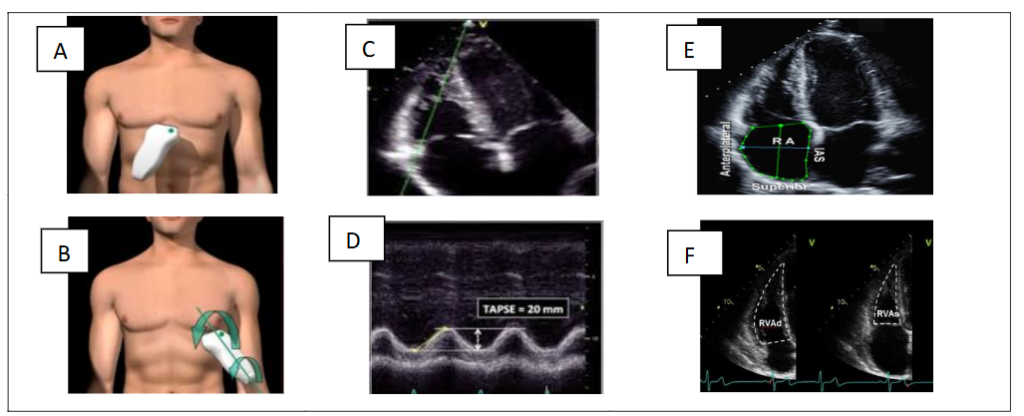

STEP 4 – DE ESTIMATION OF TRICUSPID ANNULAR PLANE SYSTOLIC EXCURSION (TAPSE), RIGHT ATRIAL (RA) SIZE AND QUALITATIVE ASSESSMENT OF RIGHT VENTRICULAR STRUCTURE AND FUNCTION

a. Tricuspid Annular Plane Systolic Excursion (TAPSE)

Tricuspid Annular Plane Systolic Excursion (TAPSE) is an angle-dependent measurement. Therefore, it is important to align the M-mode cursor along the direction of the lateral tricuspid annulus. Select a fast sweep speed. The excursion of the lateral tricuspid annulus is measured in M-mode between the end of diastole and the peak of systole and is a measure of the longitudinal systolic function of the RV in the apical four-chamber view; TAPSE <1.7 cm is highly suggestive of systolic dysfunction of the RV.

b. Right atrial (RA) dimensions

Area is measured in the apical four-chamber view at end-systole (normal values ≤ 18 cm²), on the frame just prior to tricuspid valve opening, by tracing the RA blood-tissue interface, excluding the area under the tricuspid valve annulus. RA dilatation usually indicates exposure to chronic elevations in RA pressure due to tricuspid valve disease or increased right ventricular filling pressure.

c. Right ventricular (RV) dimensions, right to left ventricular ratio and pericardial effusion

Due to the increasing preload and afterload, there is progressive right ventricular dilatation with worsening PH. All measurements are taken at the end of diastole in the right ventricular-focused view. When performing the methods to quantify right atrial and ventricular size, it is important to pay attention to the correct timing of the cardiac cycle. Measure the right ventricle at the end of diastole—when it is at its widest. The volume for the right atria is measured at the end of systole, when it is at its largest volume. It is also possible to evaluate right ventricular-left ventricular ratio, size and total left ventricular circumference, which, albeit in a generalized form, allows assessment of contractile efficiency and, in the context of the COPD hypothesis, vascular and cardiopulmonary phenotyping. The measurement is performed in apical view without foreshortening and is taken at the end of diastole. A ratio of >1 at the end of diastole suggests right ventricular dilatation. The presence of a pericardial effusion due to PH is a sign of advanced disease with a poor prognosis.

d. Fractional Area Change (FAC)

Fractional Area Change (FAC) is measured in apical four-chamber manual tracing of the RV endocardial border from the lateral tricuspid annulus along the free wall to the apex and back along the interventricular septum to the medial tricuspid annulus at the end of diastole and at the end of systole. A disadvantage of this measure is that it neglects the contribution of the RV outflow tract to overall systolic function. An RV FAC <35% indicates systolic dysfunction of the RV (figure 4).

Figure 4. Subcostal (A) and apical (B) views. Decreased tricuspid annular plane systolic excursion (TAPSE) (C-D); end-systolic RA area (E); RV FAC Fractional Area Change (F).